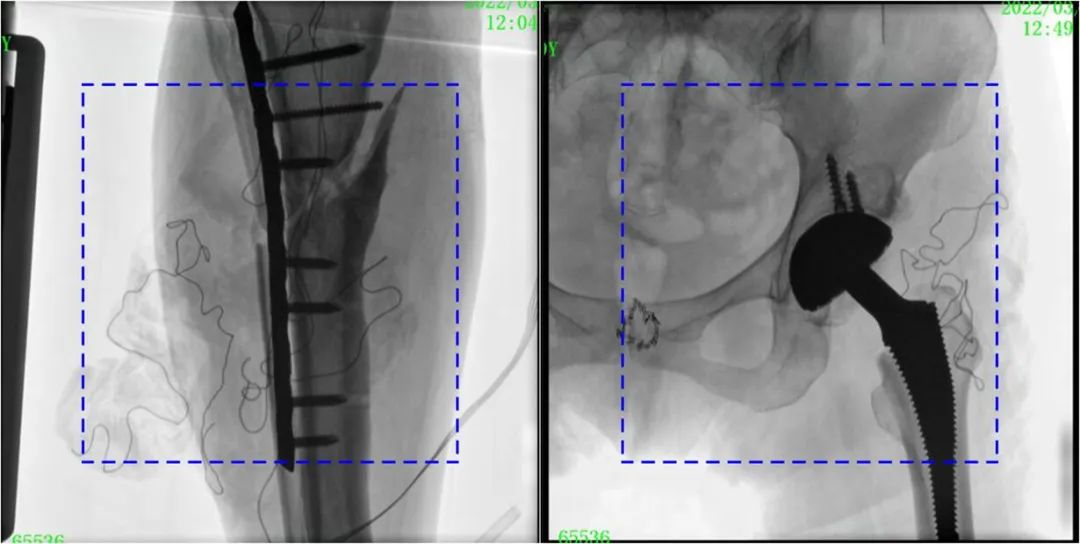

PLX119C臨床圖像與傳統(tǒng)圖像對(duì)比

注:藍(lán)色虛線內(nèi)為傳統(tǒng)21CM×21CM平板的成像區(qū)域。

大平板一體式C形臂圖像對(duì)比